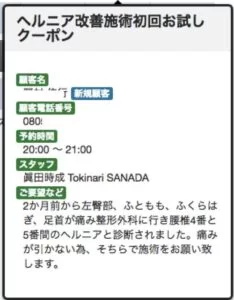

ネットでご予約の際は

2か月前から左臀部、ふともも、ふくらはぎ、足首が痛み

整形外科に行き腰椎4番と5番間のヘルニアと診断されました。

痛みが引かない為、そちらで施術をお願い致します。

とメッセージもいただきました。